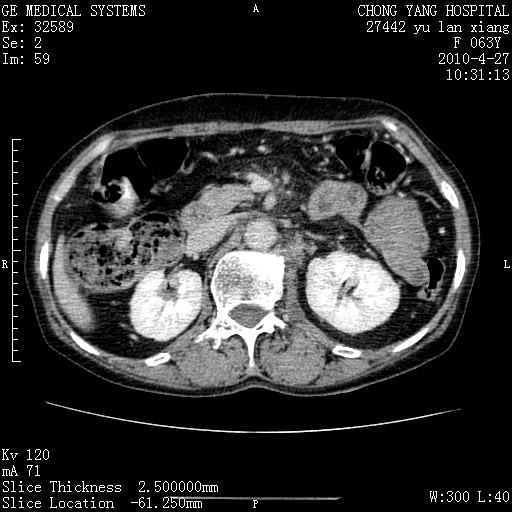

标题: CT26066:F63Y 上腹正中压痛半月,CA199:7400u/ml,MR示胰腺炎伴 [打印本页]

胰腺癌侵犯腹腔动脉干-分支、胃壁、左侧膈肌伴胰周及腹膜后淋巴结转移、胆囊切除术后。

胰腺癌侵犯腹腔动脉干-分支、胃壁、左侧膈肌伴胰周及腹膜后淋巴结转移、胆囊未显影。